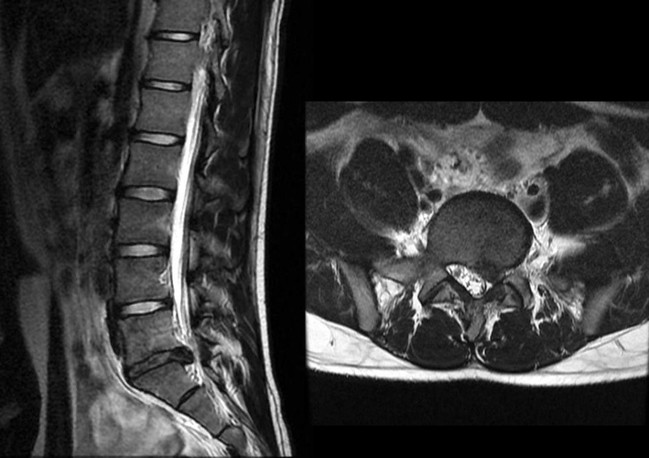

腰椎椎間板ヘルニア(MRI)

脊椎内視鏡手術は体に対する負担が少ない(低侵襲)な手術方法であり、早急な社会復帰や復職が望まれる場合、高齢社会において手術や麻酔に伴う体への負担を減らしたい方にとって、特に有用な手術方法となっています。内視鏡画像をアシストとして、より小さい傷で今までの手術と同様に行う方法から、局所麻酔で内視鏡操作のみで行う方法もでてきております。脊椎内視鏡手術は日本では1990年代後半から始まり、2010年には全国で1万件以上行われてきており、その後も社会のニーズに合わせて毎年増加してきています。 当院では腰椎の病変に対して脊椎内視鏡手術を行っております。腰椎椎間板ヘルニア、腰部脊柱管狭窄症、腰椎椎間孔狭窄症、化膿性脊椎炎などを対象としております。 脊椎内視鏡には2種類の方法があります。内視鏡視下腰椎椎間板摘出術(MED:microendoscopic disceotomy)と全内視鏡視下脊椎手術(FESS:full-endoscopic spine surgery)です。 MEDは、従来の手術を、内視鏡を用いることで小さい傷で行っているというイメージになります。全身麻酔で、2センチ程度の傷から外筒をいれて、内視鏡のアシストで、骨を削ったり、椎間板ヘルニアを摘出します。従来の手術とほぼ同等の手術効果が期待できます。 FESSは、日本では2003年ごろから開始された比較的新しい方法です。1センチ程度の傷から内視鏡を挿入して、骨を削ったり、椎間板ヘルニアを摘出します。全身麻酔ではなく、局所麻酔でも可能な方法であること、手術器具内に水を還流して行うので術後の組織の癒着が生じにくいなどの利点もあります いずれの方法も、傷は従来の手術よりも小さく、術後の体への負担も少なくなります。入院期間はリハビリテーションを含めてMEDでは2週間程度、FESSでは1週間程度となる場合が多いです。退院後、事務作業はすぐに復帰可能であり、重労働も術後4から6週後には開始可能となることが多いです。 脊椎内視鏡手術は有用な術式ですが、内視鏡の設置が必要であること、限られたスペース、手術器具で行うことから従来の手術よりも時間を要することもあります。また、出血が多い場合や、神経の癒着が強い場合などは安全のために従来の手術方法に手術中に変更することもあります。 脊椎内視鏡手術は低侵襲で、早期社会復帰が目指せる方法でありますが、内視鏡を用いたピンポイントでの手術になります。そのため術前診察、検査での痛みの原因部位の特定や、内視鏡を用いても手術の可否の判断も重要になります。腰椎疾患でお困りの方は当院受診していただいて、一緒に相談して治療していきましょう。